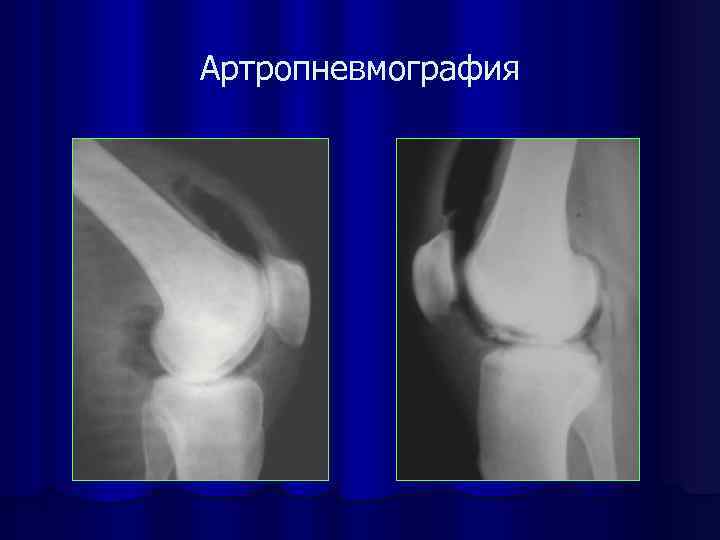

Артропневмография